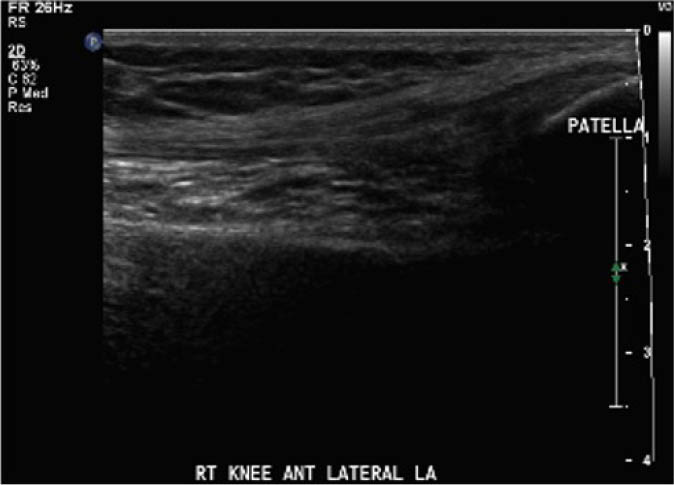

The study procedure consisted of a POCUS performed by a physiotherapist and a sonographer. The POCUS scanning procedure is presented in Appendix 1. The POCUS scans were performed in the haemophilia ambulatory clinic at patient presentation, one-week follow up, and two-week follow-up. The order of assessment was based on clinician availability. The sonographer was allowed to add additional images to the imaging protocol given their area of expertise, but the physiotherapist was instructed to acquire the images according to the scanning procedure. Ambiguous results were referred to the diagnostic imaging department for further formal investigation. Both the physiotherapist and the sonographer were blinded to each other's findings and to the results of previous scans. Methods of blinding included the use of a private clinic room and each clinician performing their assessment and documentation independently. Case report forms were placed in a sealed envelope. POCUS images were saved on the hard drive of the POCUS machine (GE Logiq) using an anonymous participant identification number.

Outcomes were assessed at presentation, one-week follow-up, and two-week follow up, resulting in a three-week study period. For the primary objective, the outcome of interest was the binary decision on the presence or absence of blood within the joint. As the technique and protocol in this study was specific to haemophilia, the criteria used to distinguish blood from effusion on ultrasound was blood presents as a complex fluid collection with mixed echogenicity and displaceable speckles on real time compression and effusion presents as simple anechoic fluid with the absence of echoes [35]. In the context of haemophilia with no symptoms suggestive of infection, complex effusions with mixed echogenicity can be assumed to represent haemarthrosis based on previous studies that have documented the accuracy of this approach using joint aspiration [35]. The physiotherapist completed the scanning protocol and interpreted the findings to make the binary assessment. Since interpreting ultrasound falls outside the scope of the sonographer, the sonographer provided an impression on the presence or absence of blood on the case report form. The radiologist read the sonographer images and provided a final diagnosis. The radiologist also reviewed the images of the physiotherapist performed ultrasound. To compare the level of agreement, the radiologist's final diagnosis was compared to the physiotherapist's interpretation. Both the physiotherapist and the sonographer recorded inconclusive ultrasound findings as absence of blood within the joint.

For the secondary objective, criteria used to evaluate image quality were appropriate pre-sets, depth, field of view, focus, gains/time gain compensation, colour and/or power Doppler, with suitable landmarks and annotation. Image quality was evaluated by the radiologist post hoc and rated as optimal, acceptable, or sub-optimal. Optimal was defined as good image quality with optimal ultrasound settings and correct annotation/documentation. Acceptable was defined as good image quality, with one image setting that should have been better optimized or a minor error in annotation/documentation that did not impact the interpretation of the POCUS scan. Sub-optimal was defined as poor image quality with more than one image setting not sufficiently optimised or an error in annotation/documentation that impacted the radiologists’ interpretation of the POCUS scan.

Post hoc analysis of the quality of the ultrasound images is shown in Table 2. The physiotherapist-performed POCUS scans demonstrated that 84.6% of the images were rated by the radiologist as optimal, 15.4% were rated as acceptable, and none were rated as sub-optimal. For the sonographer-performed POCUS scans, 88.9% of the images were rated as optimal, 11.1% were rated as acceptable, and none of the scans were rated as sub-optimal.